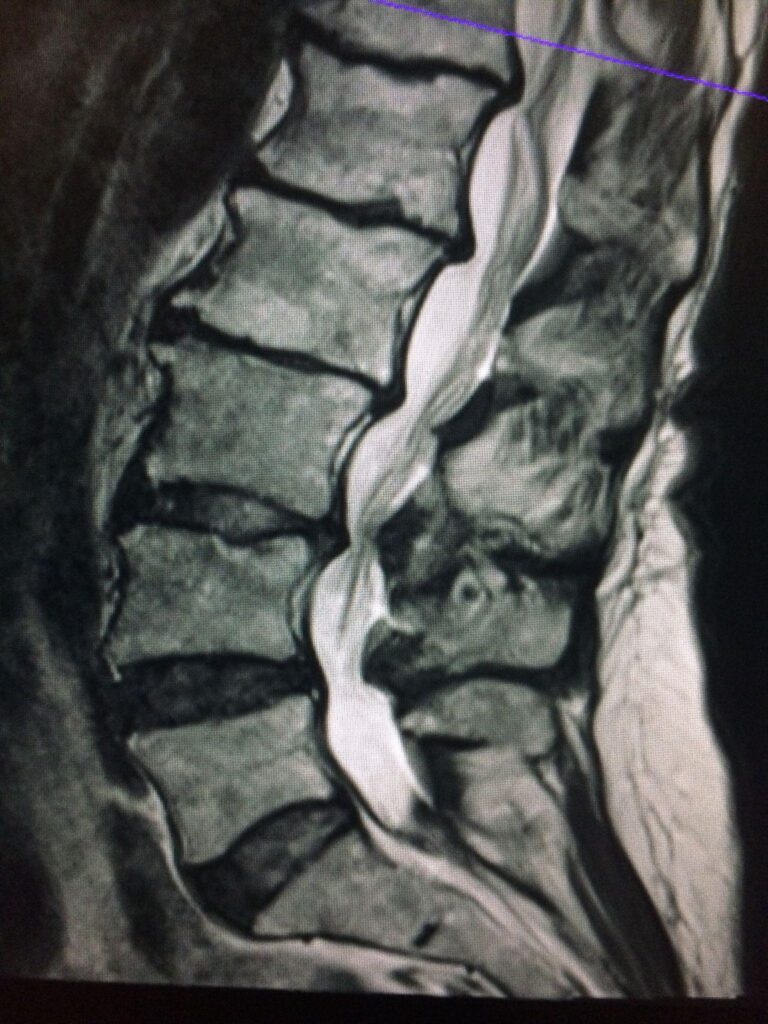

A physical exam evaluates strength, sensation, and walking pattern to determine whether nerve compression is present. MRI is the most important imaging study, as it clearly shows narrowing of the spinal canal and nerve involvement. Standing X-rays are often used to assess alignment and identify conditions such as spondylolisthesis, while additional imaging may be used in select cases.